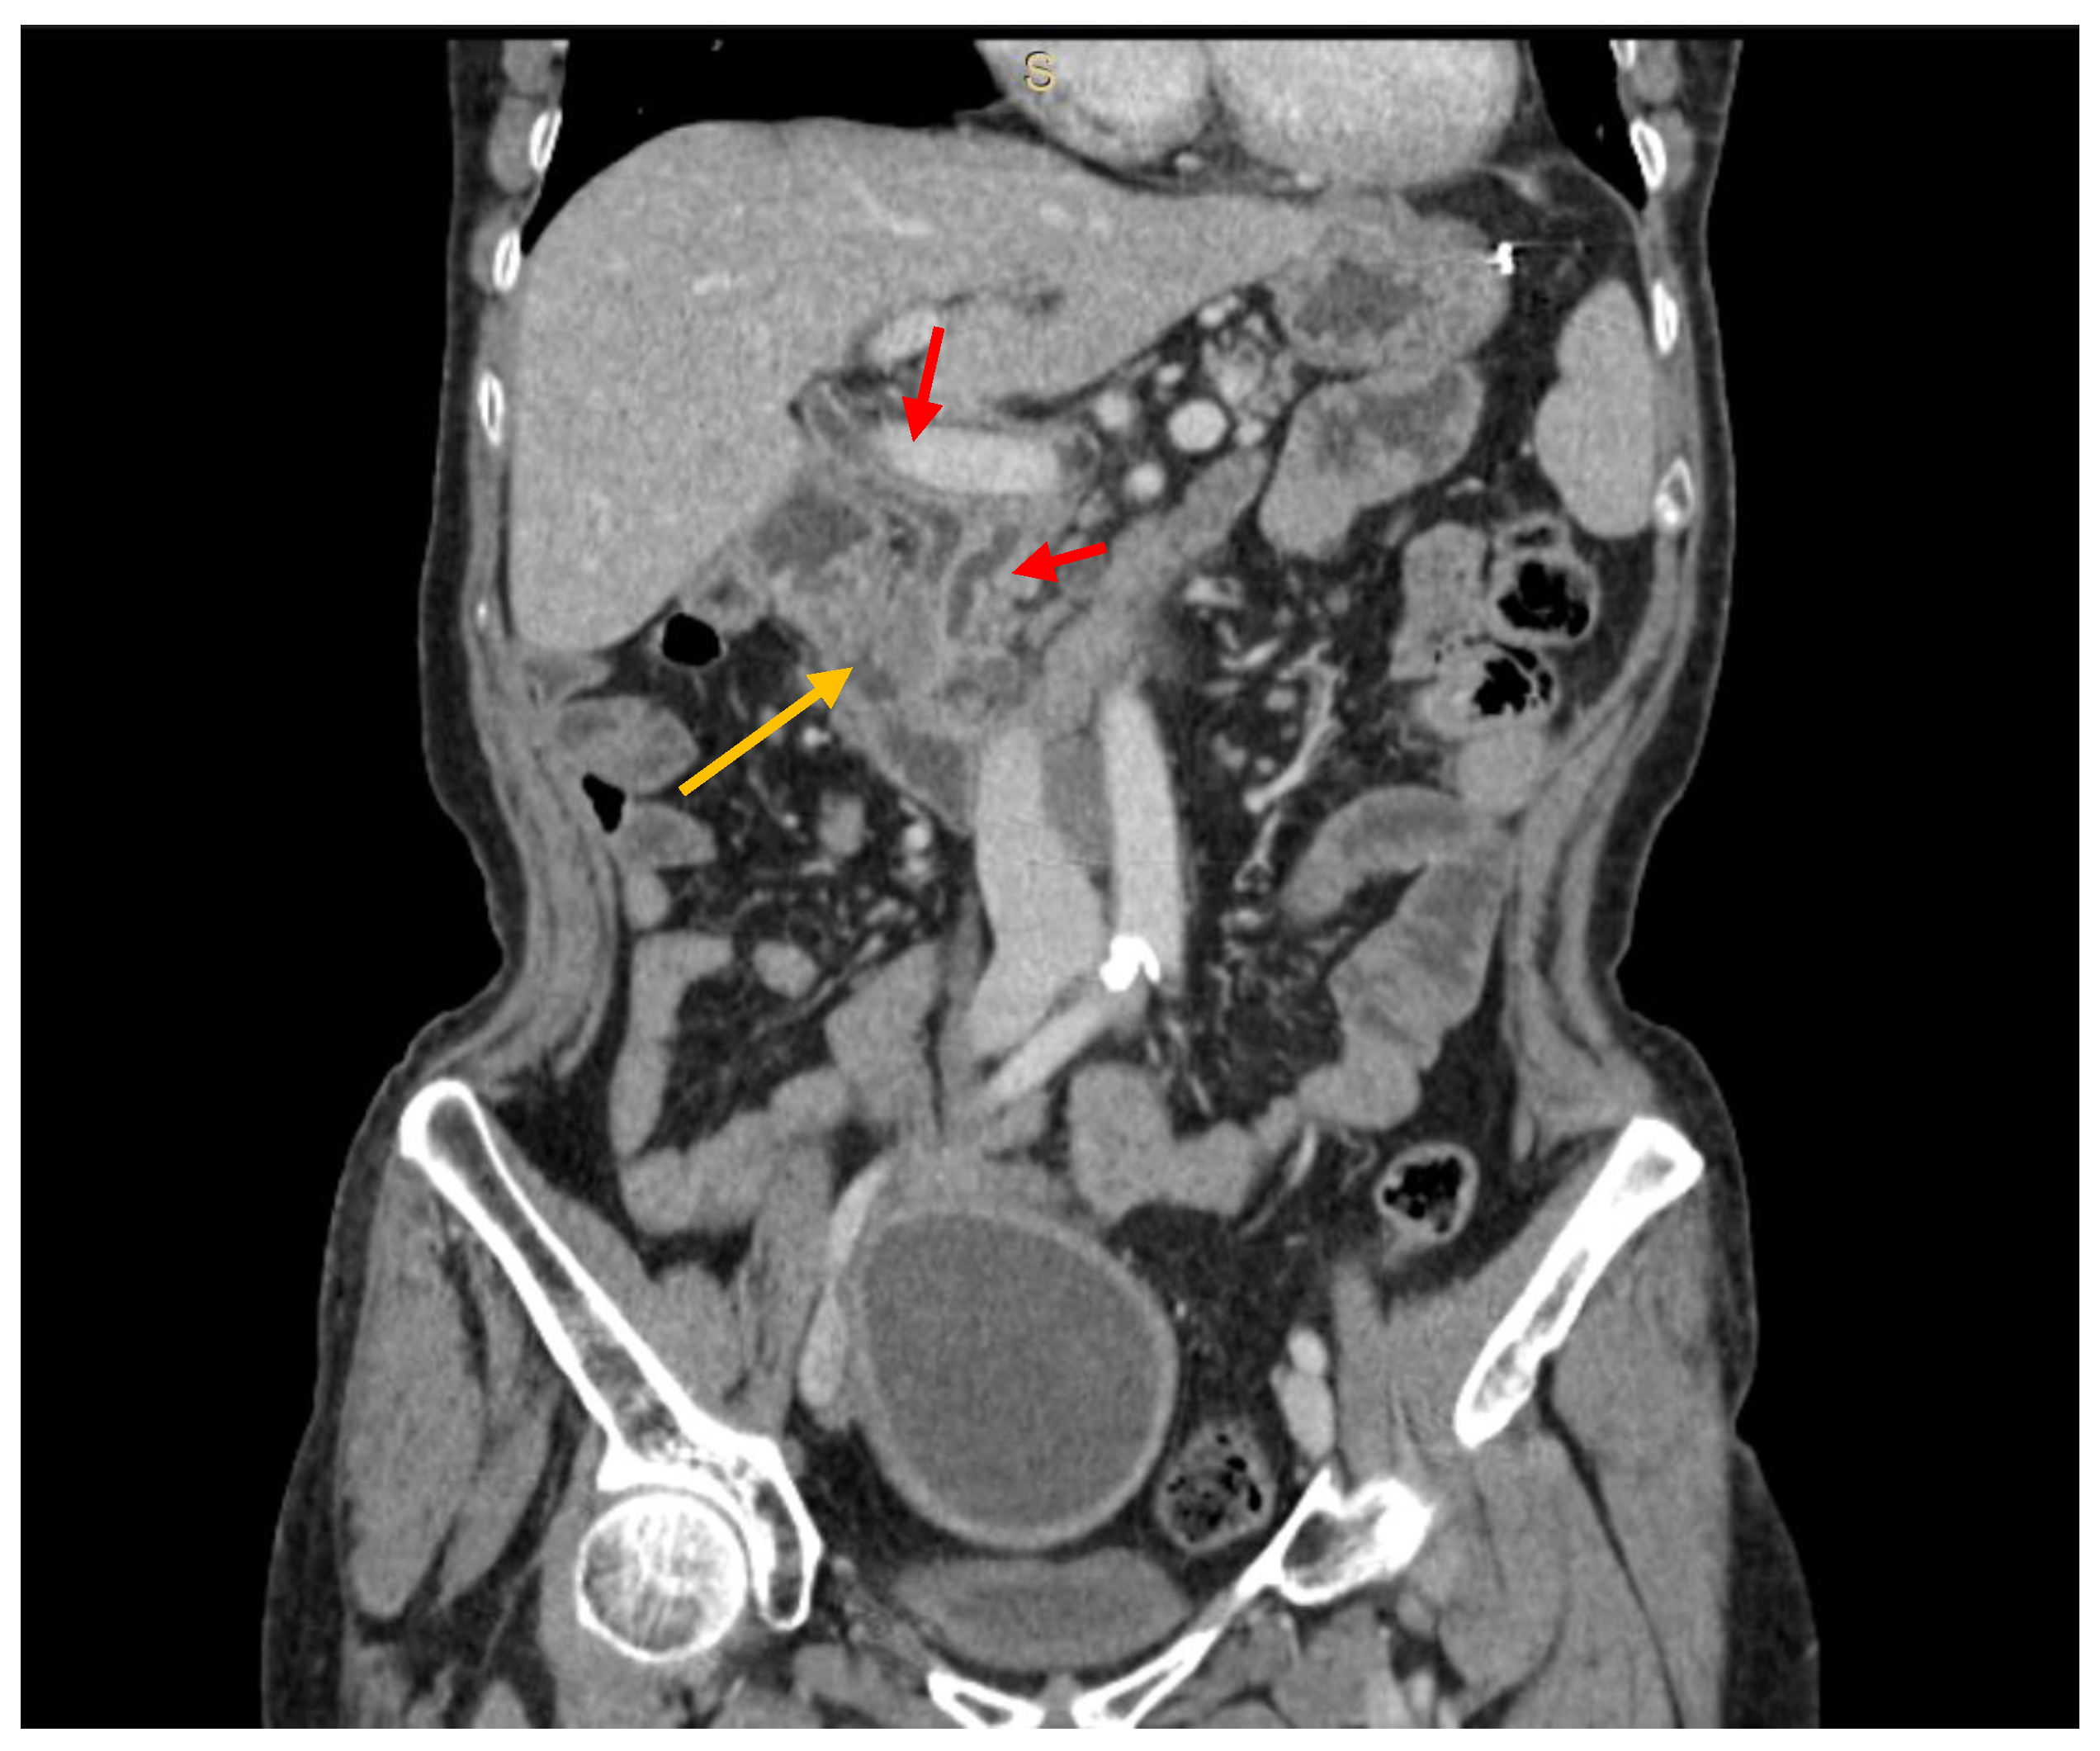

3.2. Diagnostic Work-Up

- Vincenzi, M.; Pasquotti, G.; Polverosi, R.; Pasquali, C.; Pomerri, F. Imaging of pancreatic metastases from renal cell carcinoma. Cancer Imaging 2014, 14, 5. [Google Scholar] [CrossRef]